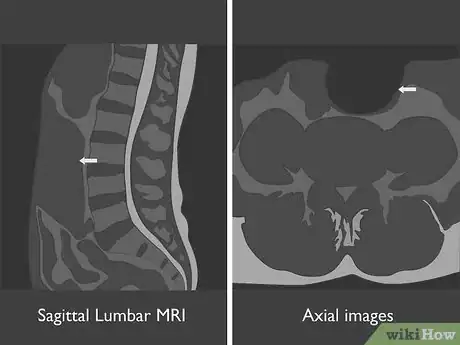

2Identify the type of MRI used in each image. At a minimum, you'll have a sagittal lumbar MRI, which is a vertical image that looks at your spine from the side. You may also have axial images, which look at a cross-section of an individual disc. Think of these as similar to slicing a tree log in sections to look at the rings on the tree. Each of these uses one of two imaging techniques:[3]

- T1-weighted images show greater contrast between tissues, which allows your doctor to more accurately diagnose disc herniation. T1-weighted images are used for sagittal MRIs but not typically for axial MRIs.

- T2-weighted images brighten the cerebrospinal fluid of your spinal canal, making it easier for your doctor to see different types of infection that might be missed by a T1-weighted image. T2-weighted images are used for both sagittal and axial MRIs.

Tip: If you see a bright, white line running down your spine on a sagittal MRI, you're looking at a T2-weighted image. The white line is the cerebrospinal fluid of your spinal canal, which holds your nerves.

3Use the sagittal image to view your entire lumbar spine. With the sagittal image, you get a better overall picture of your lumbar spine. You can identify vertebrae that are out of alignment or discs that are abnormal.[4]

4Look at axial images to view individual discs. If one or more of your discs show an abnormality, you may have axial images that show that disc in greater detail. With an axial image, you're looking at the top of the disc as seen from above.[5]

- You can tell more about the size of the nerve canals by looking at an axial image. Your doctor may use an axial image to get a clearer picture of a herniated disc.